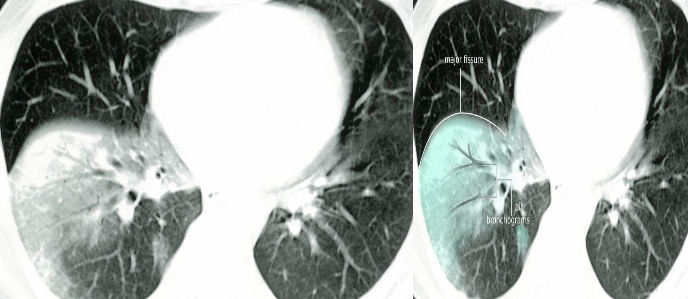

Air Bronchogram

Normally, it is not possible to identify air in bronchi within normally aerated lung, because the walls of the normal bronchi are too thin and air-filled bronchi are surrounded by air in the alveoli. However, if the alveoli are filled with fluid, the air in the bronchi contrasts with the fluid in the adjacent lung.

CT chest (axial plane; lung window) of a patient with a history of bacterial pneumonia

Opacification of much of the right lower lobe parenchyma is the result of air space consolidation. Pulmonary vessels are obscured and patent airways

(air bronchograms, white dashed line) are seen.